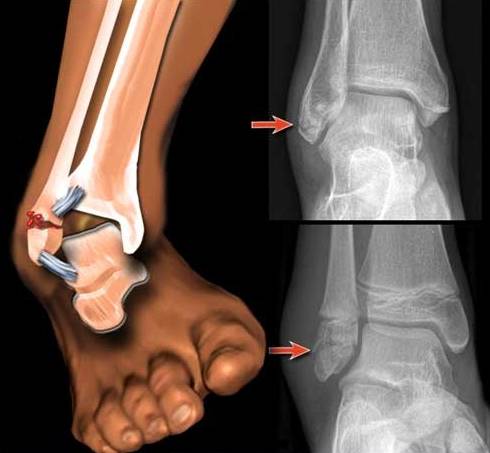

Рентген голеностопного сустава — это базовый метод обследования, который используется в процессе диагностики данной части ноги. Определение патологического состояния голеностопа или опровержение наличия болезни осуществляется с помощью рентгенографического оборудования.

Дальнейшее хранение снимка осуществляется в цифровом формате. В случае необходимости изображение голеностопа распечатывают на бумажный носитель. Для получения объективной информации о состоянии здоровья всех элементов сустава показано проведение рентгенографического исследования в 2 проекциях.

Сначала пациенту предлагают развернуть стопу так, чтобы можно было зафиксировать переднюю часть конечности и голеностопного сустава. В данном случае оценивается состояние таранной и берцовых костей, фронтального сегмента голеностопа.

Проведение этого вида рентгенографического исследования особенно актуально, если присутствует подозрение на комбинированную травму голеностопного сустава с переломом большеберцовой кости или элементов передней части стопы.

Рентген голеностопного сустава в боковой проекции выполняется в положении лежа. Данный вид исследования проводится для того, чтобы всесторонне изучить состояние конечности, зафиксировать не только голеностоп, но и пяточную, малоберцовую, плюсневую кость. Эти элементы опорно-двигательного аппарата также могут быть повреждены во время травмирования голеностопного сустава.

- Разрыв, растяжение связок. Проводится в 2 проекциях, часто с обезболивающим. Рентген при повреждении связок голеностопного сустава обнаруживает смещение таранной кости, скопление жидкости на участке повреждения, утолщение связок. При разрыве наблюдаются смещение концов кости, увеличение щели, мягких тканей.

Переломы верхней лодыжки являются наиболее распространенными травмами нижних конечностей. Они обычно вызваны изгибом стопы. Переломы, как правило, классифицируются в соответствии с Вебером.